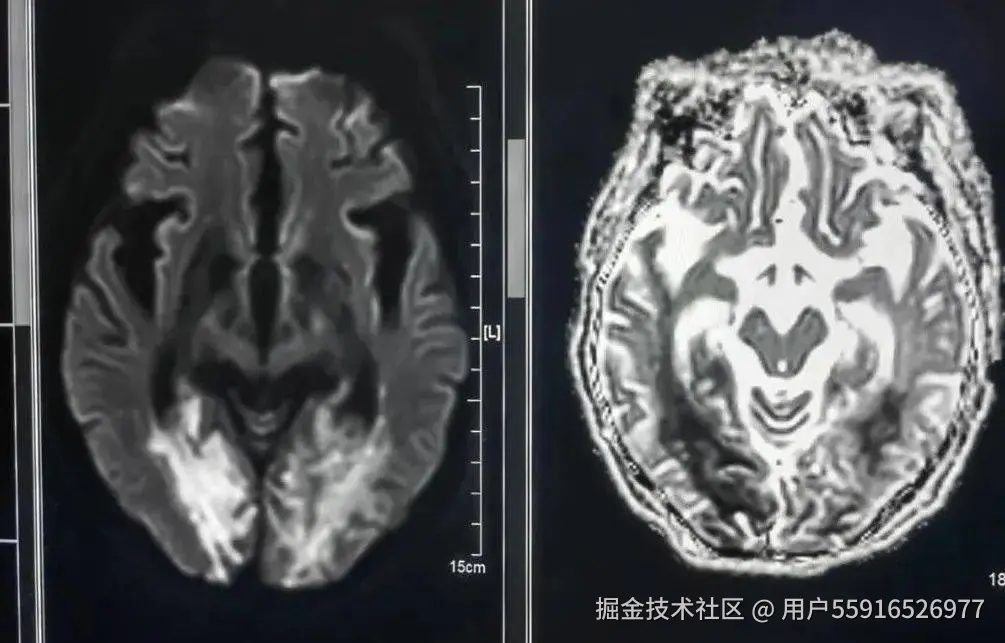

弥散成像(DWI)

DWI可以比作急性期脑缺血的“侦察兵”。能明显早于常规MRI平扫数小时发现脑缺血迹象,是脑缺血疾病筛查的项目之一。

磁敏感成像(SWI)

磁敏感加权成像(SWI)是对磁场均匀性改变的信号采集非常敏感的三维采集成像序列,具有高分辨率、高信噪比的磁共振成像(MRI)三维成像技术,越来越多的用于神经系统疾病的诊断及鉴别诊断。